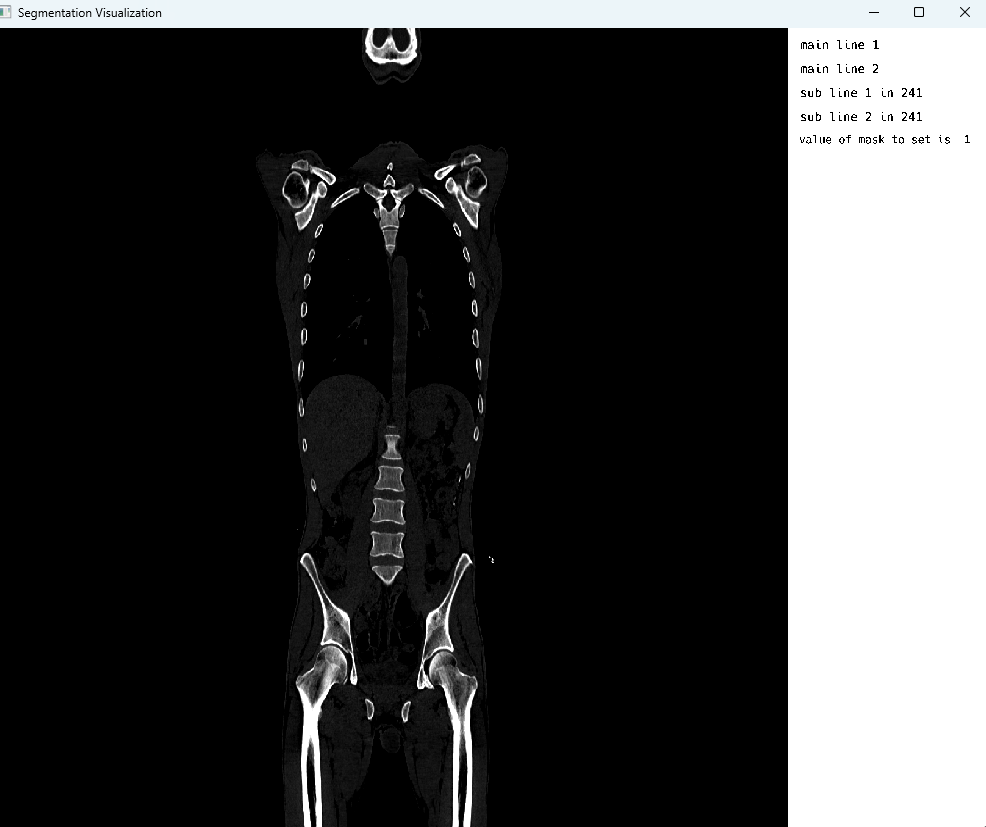

At last, an appealing result hit our sight.

Final result

Note: The image borders are intentional to emphasize the size of the visualizer which is currently defaulted to a certain width and height.